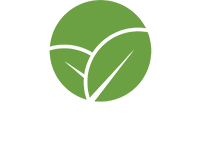

The key to nanoliposomal delivery is in the protective layer of the nanoliposome’s phospholipids. First, it is important to understand the structure of phospholipids, as this holds the key to grasping how nanoliposomes work.

In layman’s terms, each phospholipid molecule is made up of a circular “head” which likes water and a “tail” that does not. The heads are attracted to water while the tails try to avoid it, causing the phospholipids to arrange themselves in double layered lines where the heads are all outside, touching water, and the tails are “dry” in the encasement they’ve created.

In an aqueous solution (i.e. water), the phospholipids automatically self-assemble into a double layer so the hydrophobic fatty acid tails (which like to stay dry) move away from water and turn inward; whereas the water-loving phosphate head moves toward the liquid by turning toward the middle of the double layer. This results in a closed, spherical structure called a “nanoliposome” with a hollow aqueous core surrounded by a double-layer (bi-layer) membrane, which encapsulates active CBD and other nutrients into these microscopic vesicles and protects them from digestive degradation and hydrolysis in the bloodstream until they are fused into the cells.